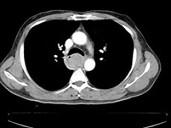

食管癌的最常见的好发部位是()A.颈段B.上段C.中段D.下段E.贲门

问题 食管癌的最常见的好发部位是()

选项 A.颈段 B.上段 C.中段 D.下段 E.贲门

答案 C